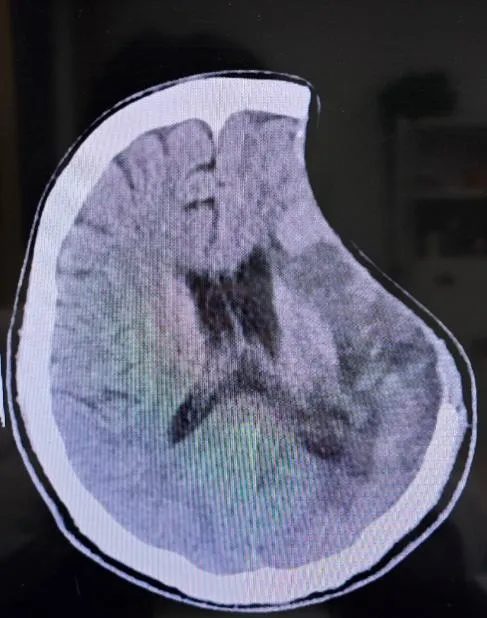

男性,27岁,2个月前因突发脑出血,当地医院行去骨瓣减压术+颅内血肿清除术+硬脑膜修补术,现为颅骨修补术前来我院,考虑年轻男性患者,术后需继续经颅磁刺激治疗,以改善认知功能,恢复患侧肢体功能障碍,刘博主任团队全面评估,决定采用全PEEK系列整体解决方案。手术过程顺利,术后患者头颅恢复原貌,头颅CT示PEEK骨板在位,未见出血和皮下积液。

术后CT